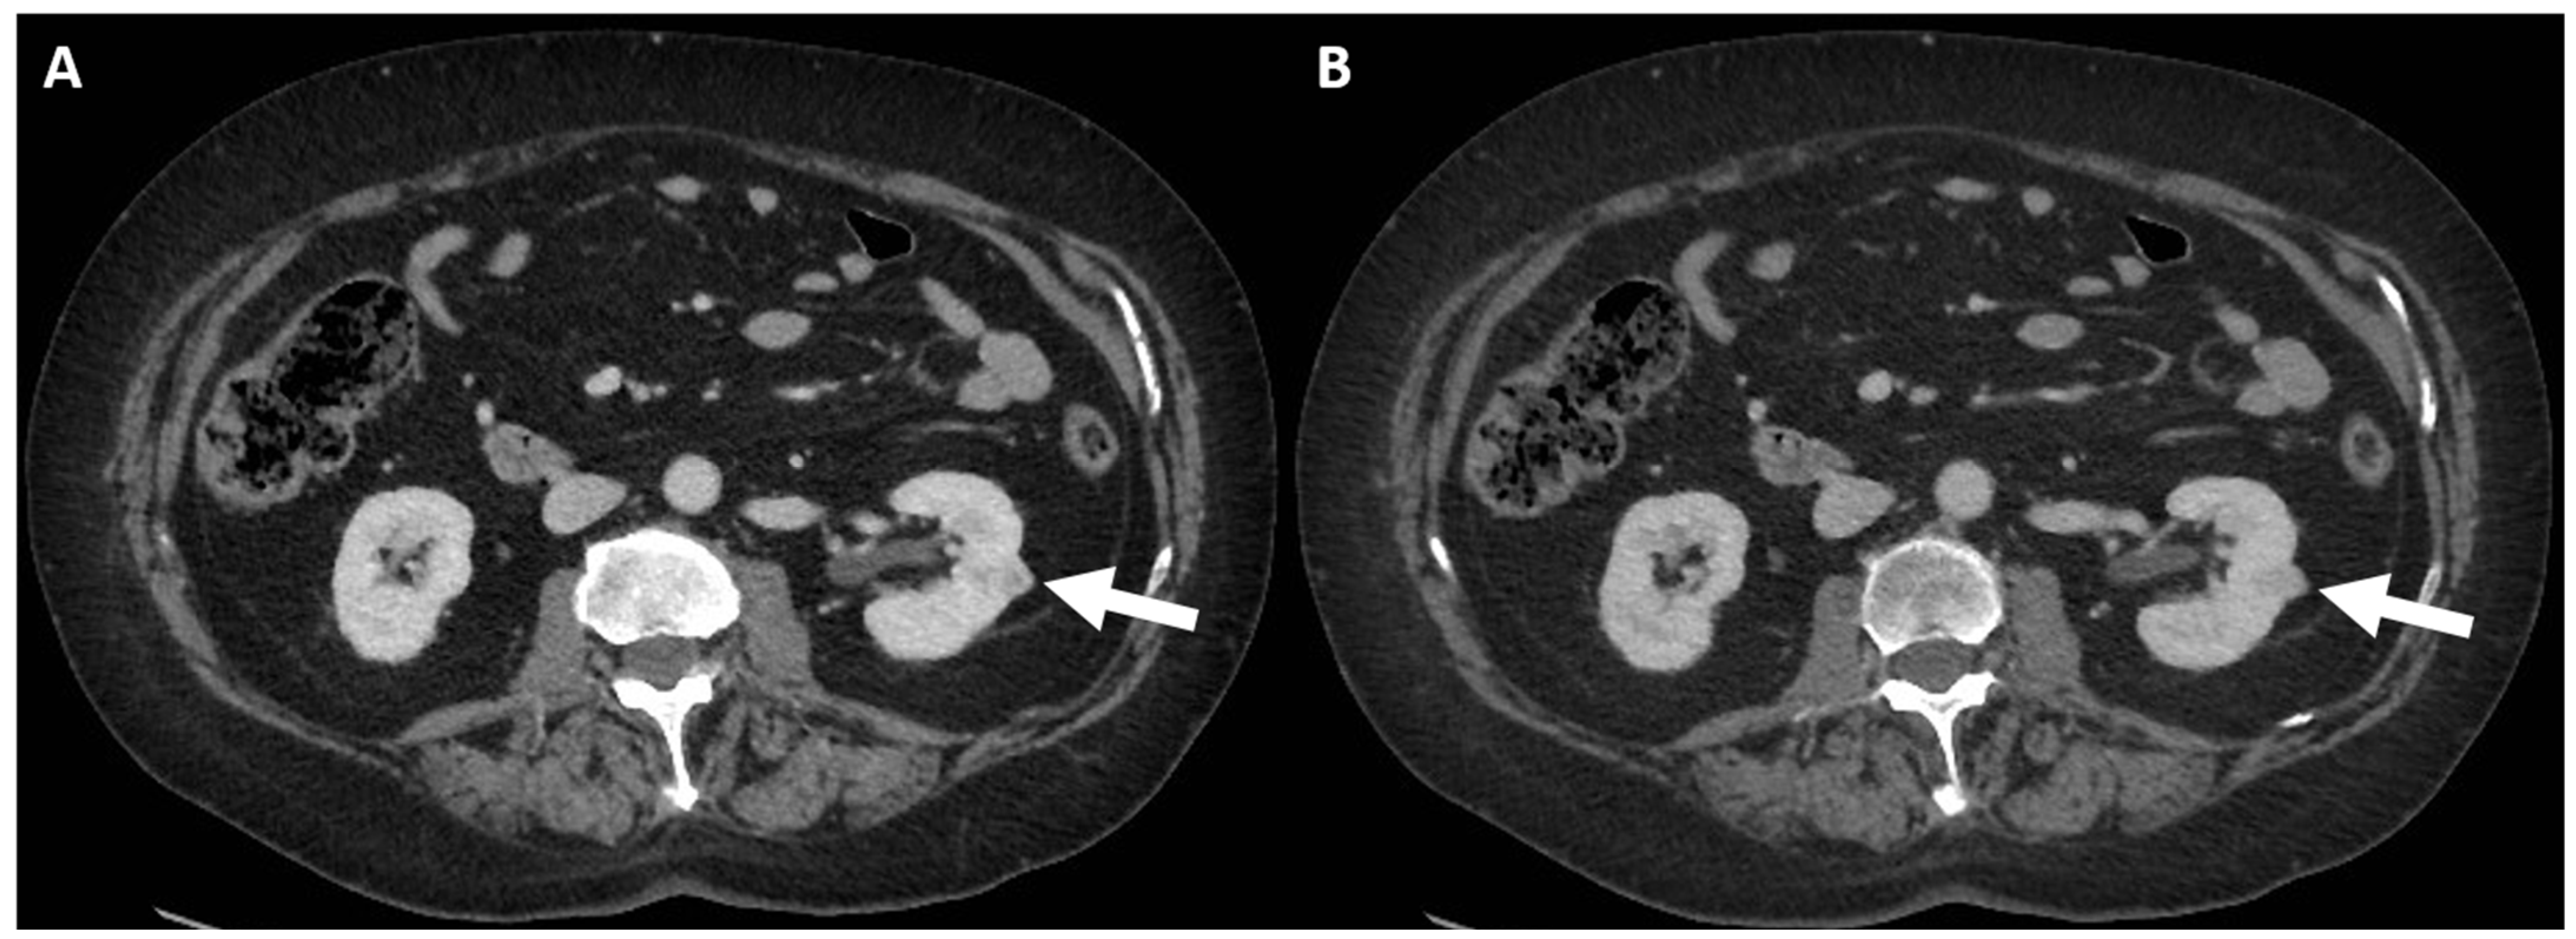

4.2. Macroscopic Fat

3. Contrast-Enhanced Ultrasound Assessment